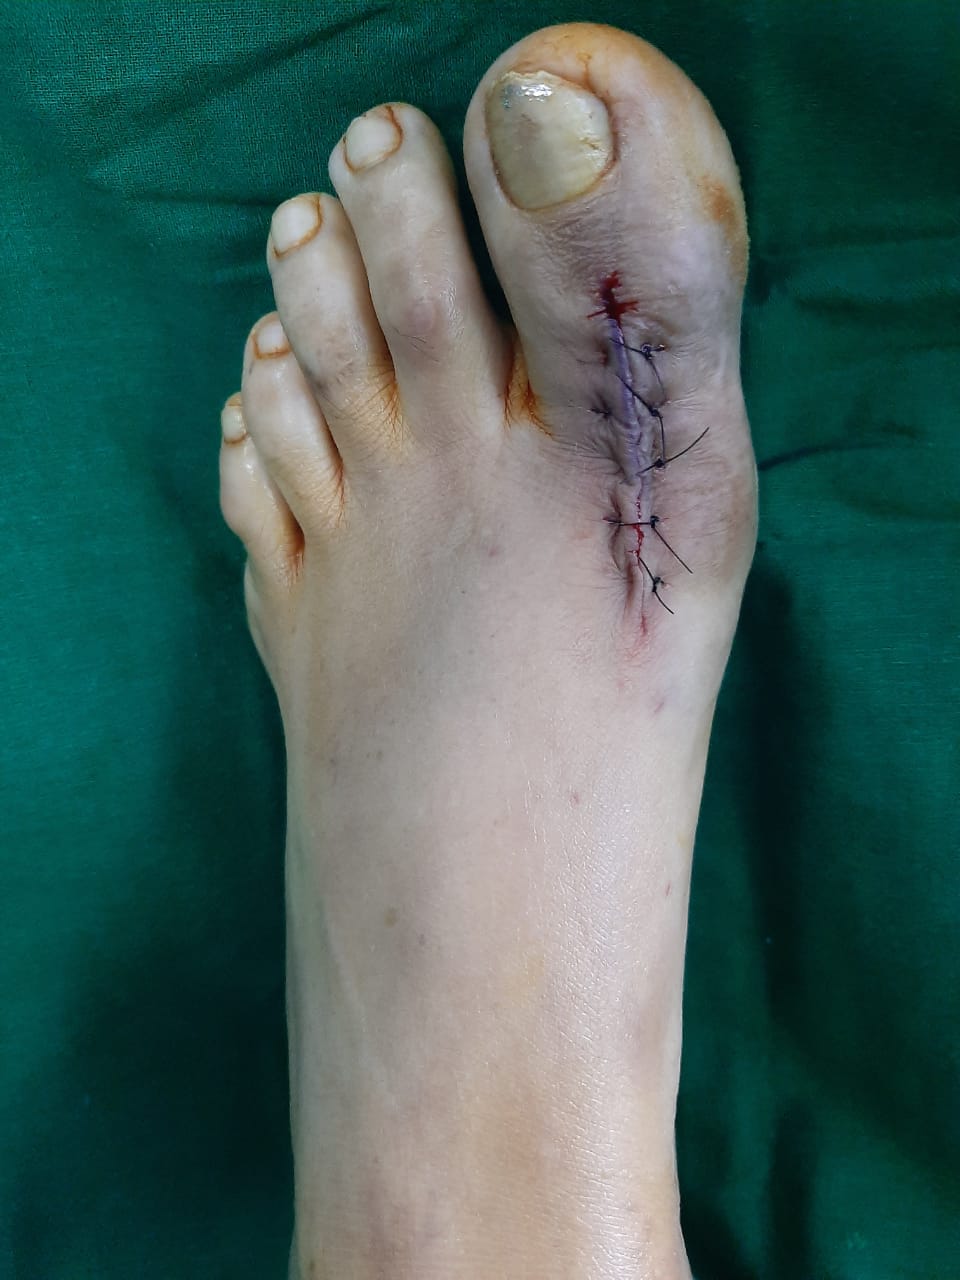

Patient’s Successfully Treated with Diabetic Foot Problems